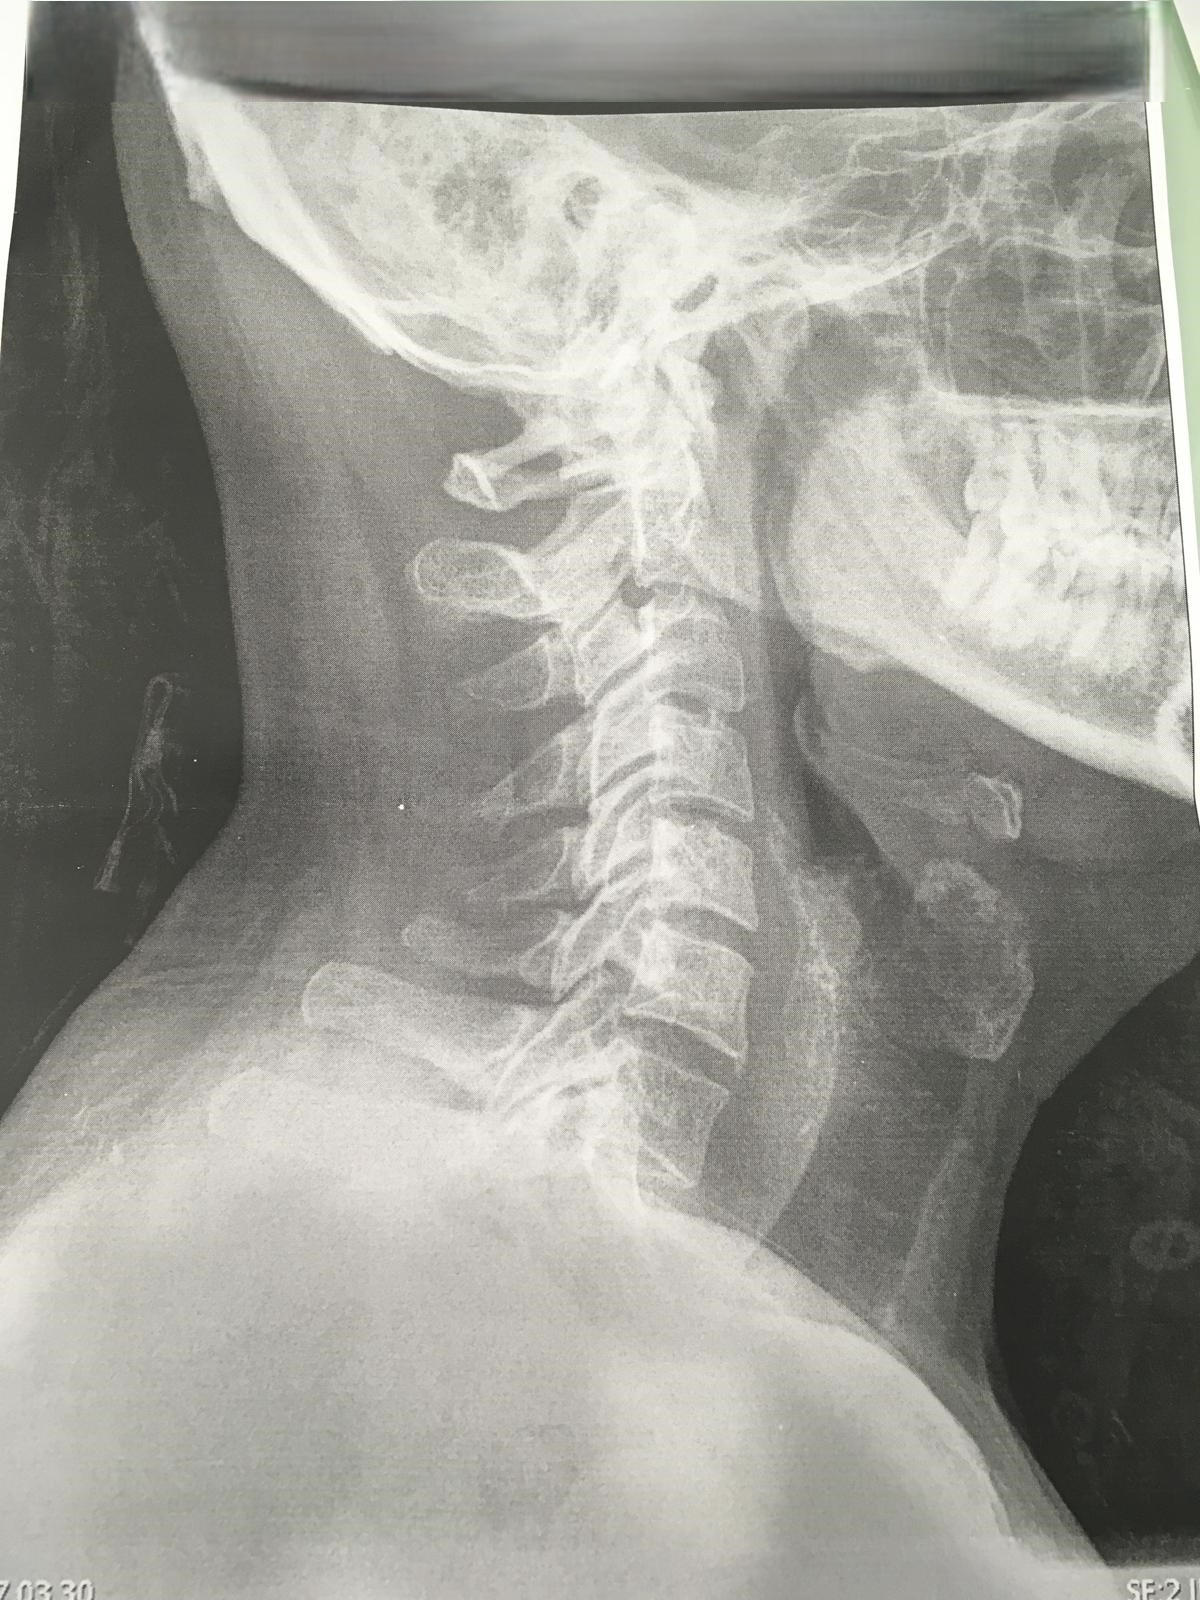

En C5-C6 cambios degenerativos con complejo disco osteofitario que condiciona estenosis moderada del canal raquídeo cervical, apreciando signos de mielopatía compresiva. Estenosis foraminal bilateral moderada en C5-C6 e izquierda leve en C6-C7 |

Se aprecia la prótesis de disco colocada entre C5 y C6 | ||||